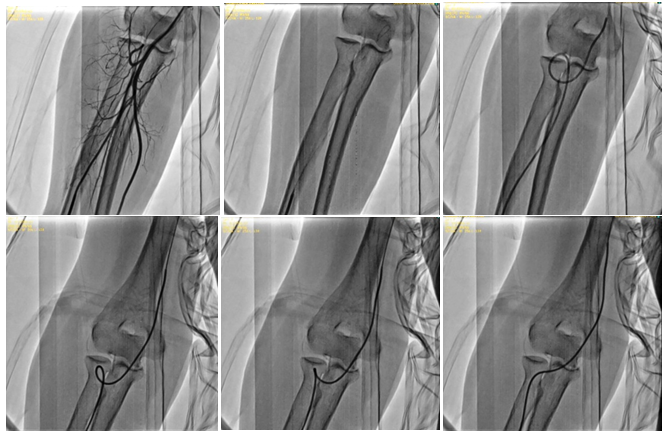

Figure 4 (a-f): Radial artery loop and necessary steps to overcome the loop.

a. Radial artery loop angiography.

b. Advancement of the 0,014” hydrophilic coronary wire.

c. Diagnostic JR 4 (5F) advancement in the radial artery loop.

d. Rotation and pull-back of the catheter (0,014” coronary wire is changed with standard 0,035” diagnostic wire to enable better support).

e. Further rotation and pull-back of the catheter.

f. Straightening of the radial artery loop.